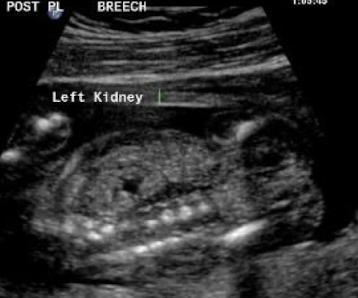

what plane was this taken in?

transverse